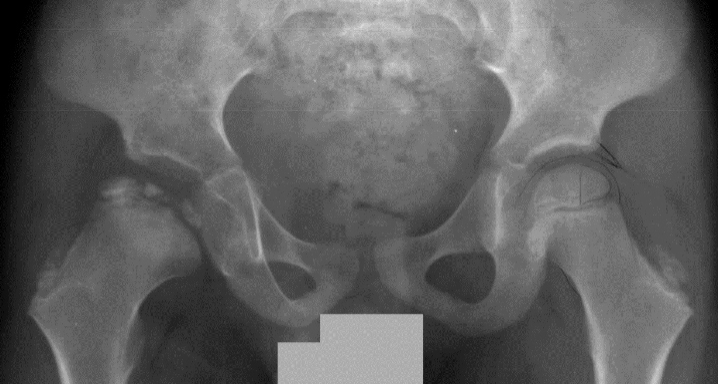

Example of Hip Distraction Treatment

Eleven-year-old boy with late-onset Perthes disease. He previously underwent a shelf procedure at another institution that failed.

X-ray shows the hip during hip distraction. Note that the femoral head is completely contained inside the hip cup.

These X-rays show the hip one year after hip distraction treatment. The hip has full range of motion, and the boy is not in pain.What are some of the logistical issues for children undergoing hip distraction treatment?